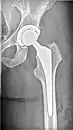

![]() | |

| X-ray of hip with femoral head osteonecrosis | |